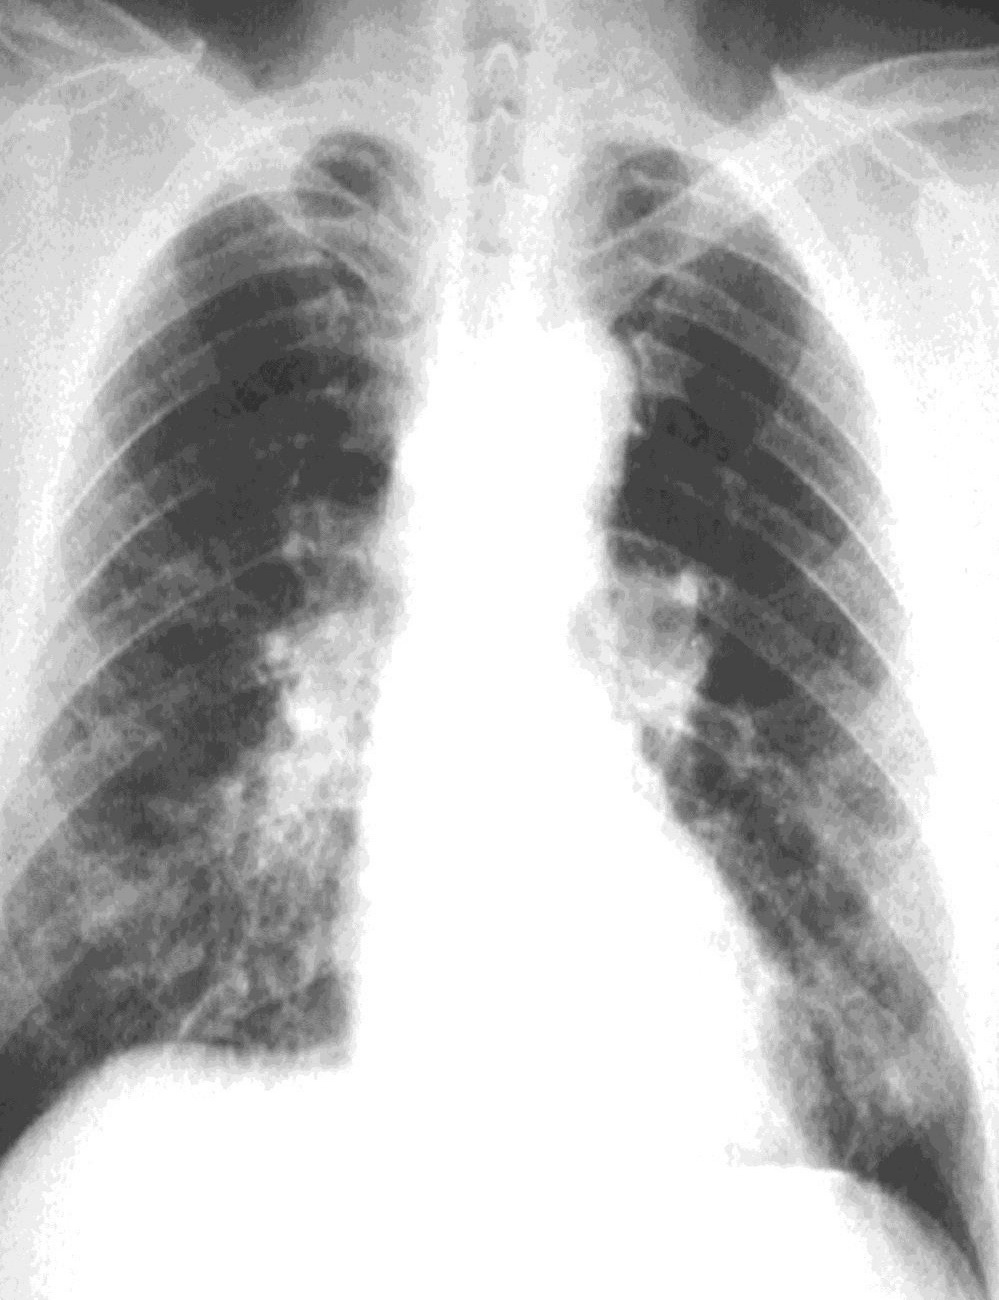

비정상적인 흉부 엑스레이와 그 해석은 폐 섬유증의 존재를 확립하는 데 가장 중요한 요소로 남아있다.[11] 소견은 일반적으로 폐 기저부에 주로 나타나는 작고 불규칙한 실질 불투명으로 나타난다. ILO 분류 시스템을 사용하면 "s", "t", 및/또는 "u" 불투명이 우세하다. CT 또는 고해상도 CT(HRCT)는 폐 섬유증(및 기저 흉막 변화)을 감지하는 데 일반 방사선 촬영보다 더 민감하다. 석면폐증을 앓는 사람의 50% 이상이 흉벽과 폐 사이의 공간인 벽측 흉막에 반점을 형성한다. 일단 나타나면 석면폐증의 방사선학적 소견은 추가적인 석면 노출이 없더라도 천천히 진행되거나 정체될 수 있다.[26] 급속한 진행은 다른 진단을 시사한다.